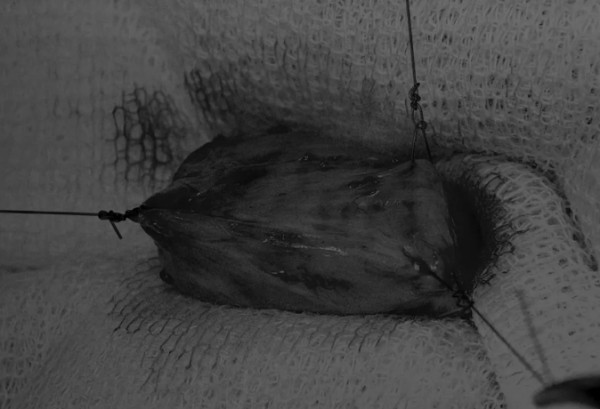

图1 将膀胱从腹腔中取出,用无菌外科敷料隔离。为了防止膀胱滑入腹部,可在膀胱顶部放置一根固定缝线,由助手通过止血钳夹住固定缝线做持续牵引